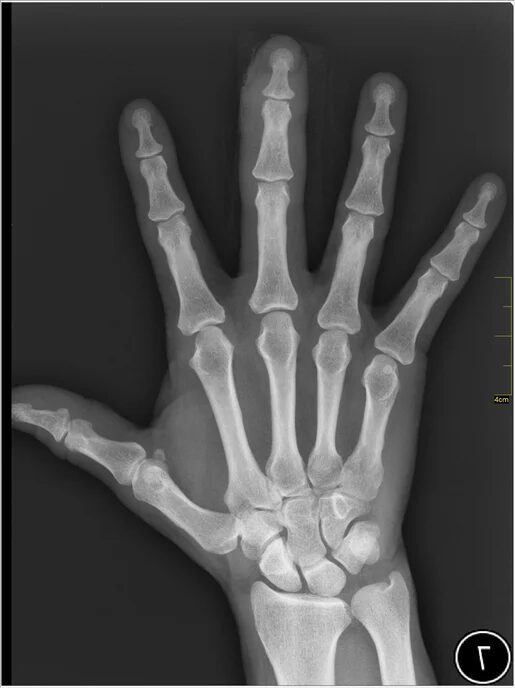

Many people are starting to use AI chatbots, like ChatGPT from OpenAI and Gemini from Google, to ask questions about their health and get advice on medical issues. Some folks even use questionable apps that claim to check if someone’s genitals are free from disease using AI. Recently, users on the social media platform X (formerly known as Twitter) have been encouraged to upload their X-rays, MRIs, and PET scans to an AI chatbot called Grok to help interpret these medical images.

Elon Musk, the owner of X, has encouraged users to upload their medical images to Grok, admitting that the AI’s results are still in the early stages but claiming that it will improve over time. The idea is that by submitting medical images, users can help the AI become better at interpreting scans accurately. However, it’s unclear who will have access to the data collected by Grok. According to Grok’s privacy policy, X shares some user information with a number of “related” companies, but it doesn’t specify who those companies are.